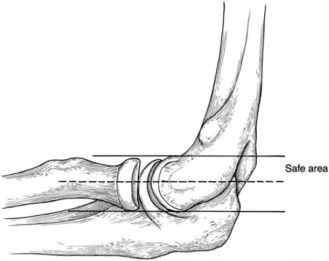

The Ellman classification differentiates between bursal-sided tears (Ellman classification B) and articular-sided tears (Ellman classification A), and also between those that are less than 3 mm in depth (Ellman classification I), between 3 and 6 mm in depth (Ellman classification II), and greater than 6 mm in depth (Ellman classification III). If a tear is bursal-sided and less than 3 mm in depth (BI), this can be treated with arthroscopic debridement of the tear (Answer A). If it is bursal-sided and greater than 3 mm in depth (BII as in this patient or BIII), this should be treated with arthroscopic rotator cuff repair (Answer C). In addition, subacromial decompression should be considered with all bursal-sided tears, and acromioplasty should be performed if the patient has a type II or type III acromion or has anterior acromion bone spurs. If the tear is articular-sided and less than 6 mm (Ellman classification AI or AII), this can be debrided. If the tear is articular-sided and greater than 6 mm in depth (Ellman classification AIII), this should be repaired. Subacromial decompression and acromioplasty may not be necessary in the case of articular-sided tears. Refer to Table 2–1 and Figure 2–10 for a summary of the Ellman classifications and the indicated surgical treatment after failure of conservative treatment.

Figure 2–10 Potential treatment algorithm for partial-thickness rotator cuff tears. (Reproduced with permission from Shi LL, Mullen MG, Freehill MT, et al. Accuracy of Long Head of the Biceps Subluxation as a Predictor for Subscapularis Tears. Arthroscopy 2015;32(4):615-619.)